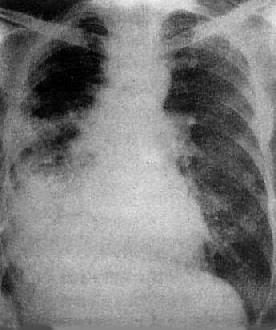

肺泡癌

图3-1-31 肺泡癌

两肺出现大小不等多发小结节影,右中下肺野病灶融合成一片致密影肋膈角及膈均不见,指明有胸腔积液

(3)细支气管肺泡癌:早期可表现为孤立的结节状或肺炎样浸润影,其中可见含气的支气管或小的透明区,透明区系由于部分肺泡尚含有空气所致。晚期可表现为弥漫性病变,在一肺或两肺出现大小不等、境界不清的结节状或斑片状影,为腺泡结节状占位病变(图3-1-31)。进一步发展,这些病灶可以融合成大片絮状影,形成癌性实变。